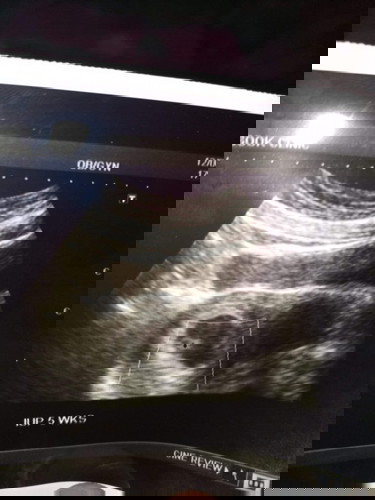

ของเราอายุครรภ์นับจากประจำเดือนก็ 7w 5d แล้วค่ะ แต่คุณหมอซาวด์ให้ บอกได้ 5w เจอตัวเด็กและหัวใจแล้ว จุดดำๆคือหัวใจค่ะ